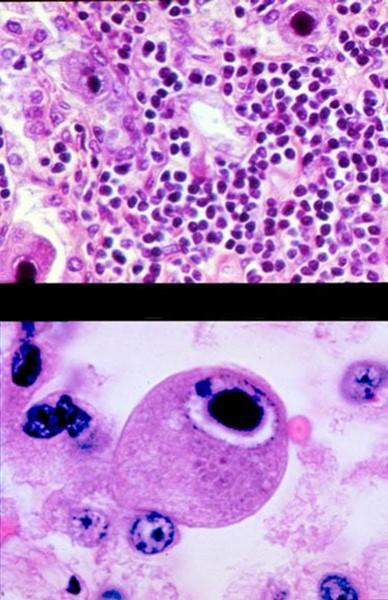

lymphs and MPs

what is the big CNS invader when someone has HIV

toxoplasma

what type of stain is this

India ink

what are these microabscesses caused by

cryptococus